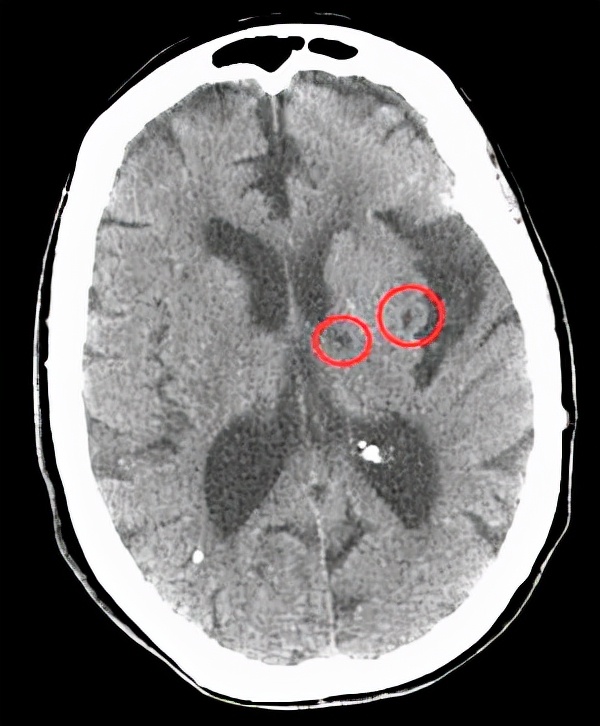

一、脉络丛钙化。

在报告单上经常可以看到脉络丛钙化这个名词,很多人一看:脑子里面有钙化了,一定是不好的东西。

真是这样吗?其实并不用害怕,脉络丛钙化可能并没有什么问题,只是你的大脑血管有些老化而已。

而随着年龄的增长脉络丛可能出现钙化,通常都是生理性的,并不需要太在意。

另外也要看具体情况,有没有其他的症状体征,如果什么问题都没有,一般是不需要处理的,也不需要用药。

但是如果有症状呢,身体真的感觉不一样了,脉络丛钙化可能也预示着某些肿瘤的出现,甚至和脑积水也相关,这个时候就不要轻易放过了。

总之具体情况具体分析,不能以偏概全,也不要吓唬自己。